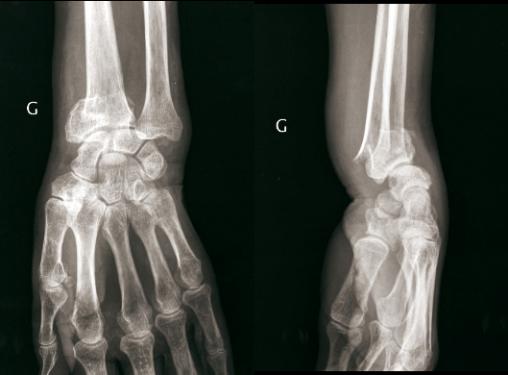

© Henry Coudane, Frédéric Éloy (La Revue du Praticien) Fracture extra-articulaire à déplacement postérieur. (À gauche) Radio de face. (À droite) Radio de profil.